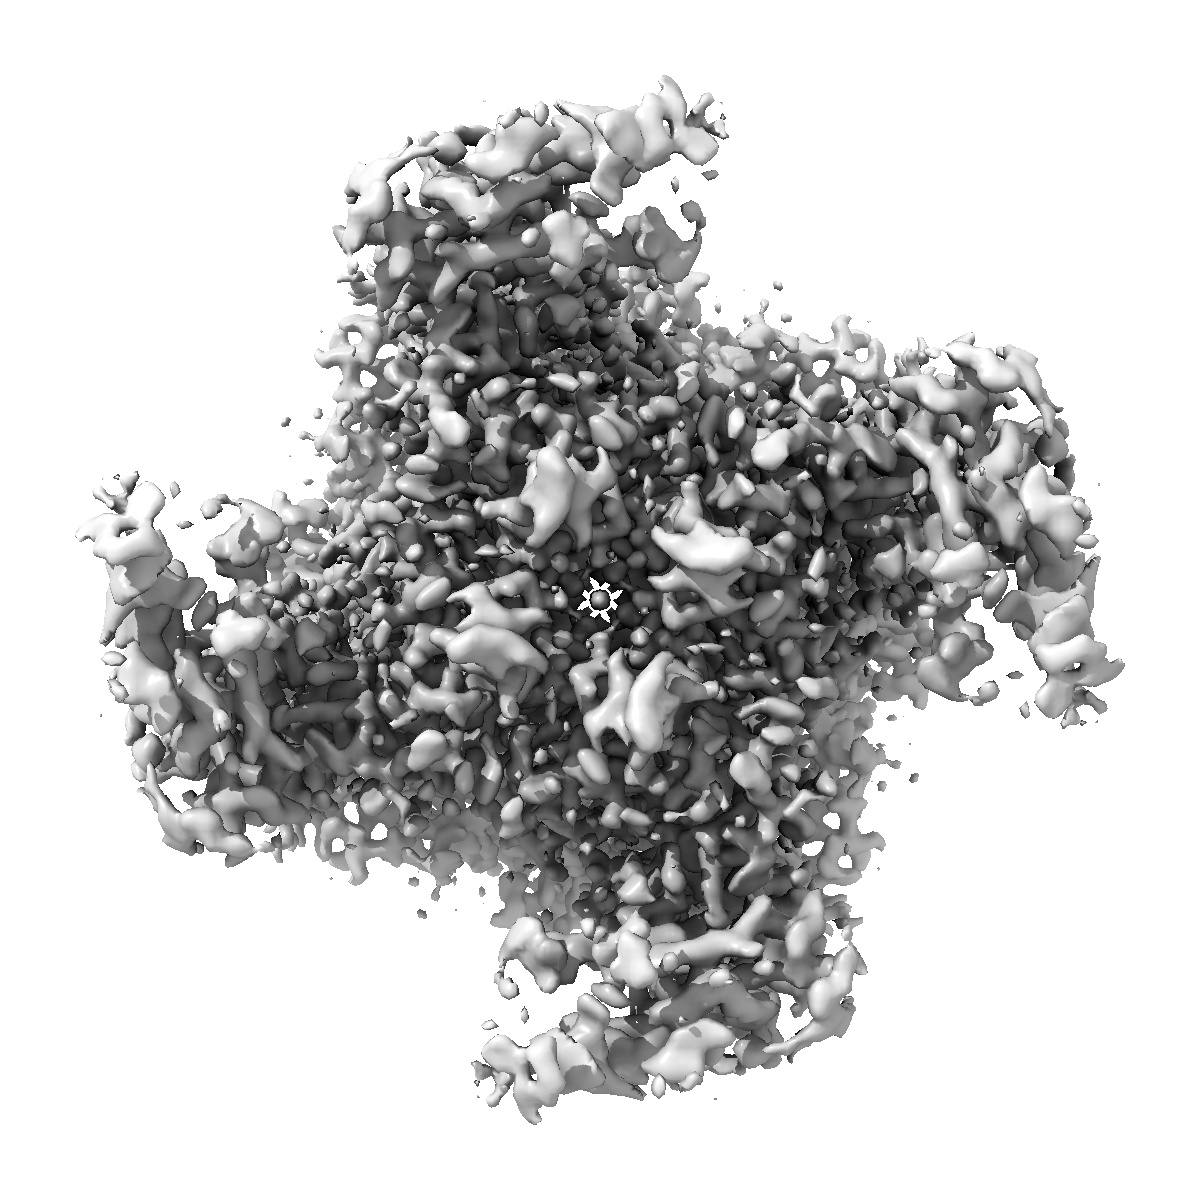

TRPML1 in complex with compound 11

Single-particle2.1 Å

High throughput cryo-EM provides structural understanding for modulators of the lysosomal ion channel TRPML1.

(2025) Structure , 33 , 1374 - 1385.e7